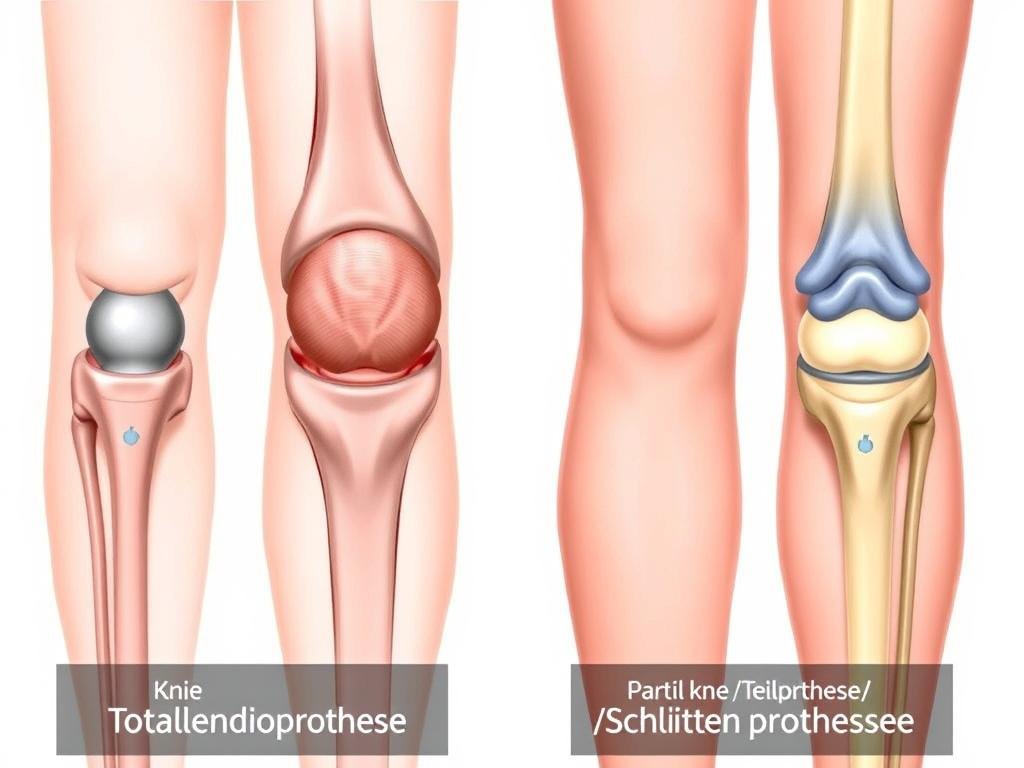

Vergleich zwischen gesundem Kniegelenk und fortgeschrittener Kniearthrose

Arten von Kniegelenksprothesen

Je nach Ausmaß der Arthrose und den betroffenen Bereichen des Kniegelenks kommen unterschiedliche Prothesentypen zum Einsatz. Die Wahl des geeigneten Implantats hängt von verschiedenen Faktoren ab, darunter das Alter des Patienten, seine körperliche Aktivität, die Knochenqualität und die spezifische Ausprägung der Arthrose.

Übersicht: Vollprothese (links) und Teilprothese (rechts)

Vollprothese (Knie-Totalendoprothese)

Bei der Knie-Totalendoprothese (K-TEP) werden alle Gelenkflächen des Kniegelenks ersetzt. Dies umfasst sowohl die femorale (oberschenkelseitige) als auch die tibiale (schienbeinseitige) Komponente. Die Oberschenkelkomponente besteht aus Metall und ahmt die natürliche Form der Femurkondylen (Oberschenkelrollen) nach. Die Schienbeinkomponente besteht aus einer Metallplatte mit einem Polyethylen-Inlay als Gleitfläche. In manchen Fällen wird auch die Rückfläche der Kniescheibe (Patella) durch eine Kunststoffkomponente ersetzt.

Man unterscheidet zwischen ungekoppelten und gekoppelten Vollprothesen:

- Ungekoppelte Prothesen: Die Stabilität wird durch die körpereigenen Bänder gewährleistet. Sie erlauben neben Beugung und Streckung auch eine gewisse Rotation im Kniegelenk.

- Gekoppelte Prothesen: Die Prothesenkomponenten sind mechanisch miteinander verbunden, was mehr Stabilität bietet, aber die Beweglichkeit einschränkt. Sie kommen zum Einsatz, wenn der Bandapparat stark geschädigt ist.

Teilprothese (Schlittenprothese)

Wenn nur ein Bereich des Kniegelenks von Arthrose betroffen ist, kann eine Teilprothese (auch Schlittenprothese oder unikondyläre Prothese genannt) ausreichend sein. Dabei wird nur der geschädigte Teil des Gelenks ersetzt, während die gesunden Bereiche erhalten bleiben. Dies ermöglicht eine natürlichere Kniefunktion und bessere Beweglichkeit.

Folgende Arten von Teilprothesen gibt es:

- Mediale Schlittenprothese: Ersetzt den inneren Gelenkanteil (bei O-Beinen)

- Laterale Schlittenprothese: Ersetzt den äußeren Gelenkanteil (bei X-Beinen)

- Patellofemorale Prothese: Ersetzt nur die Gleitfläche zwischen Kniescheibe und Oberschenkel